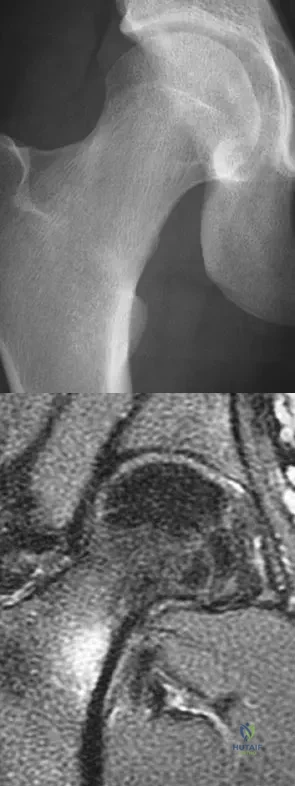

Question 63

A 21-year-old collegiate female cross-country athlete reports right hip pain that begins about 12 miles into a run, followed by pain resolution when she discontinues running. However, each time she tries to resume a running program, she experiences recurrence of pain deep in the anterior groin. A plain radiograph and MRI scan are shown in Figures 8a and 8b. Management should consist of

Explanation